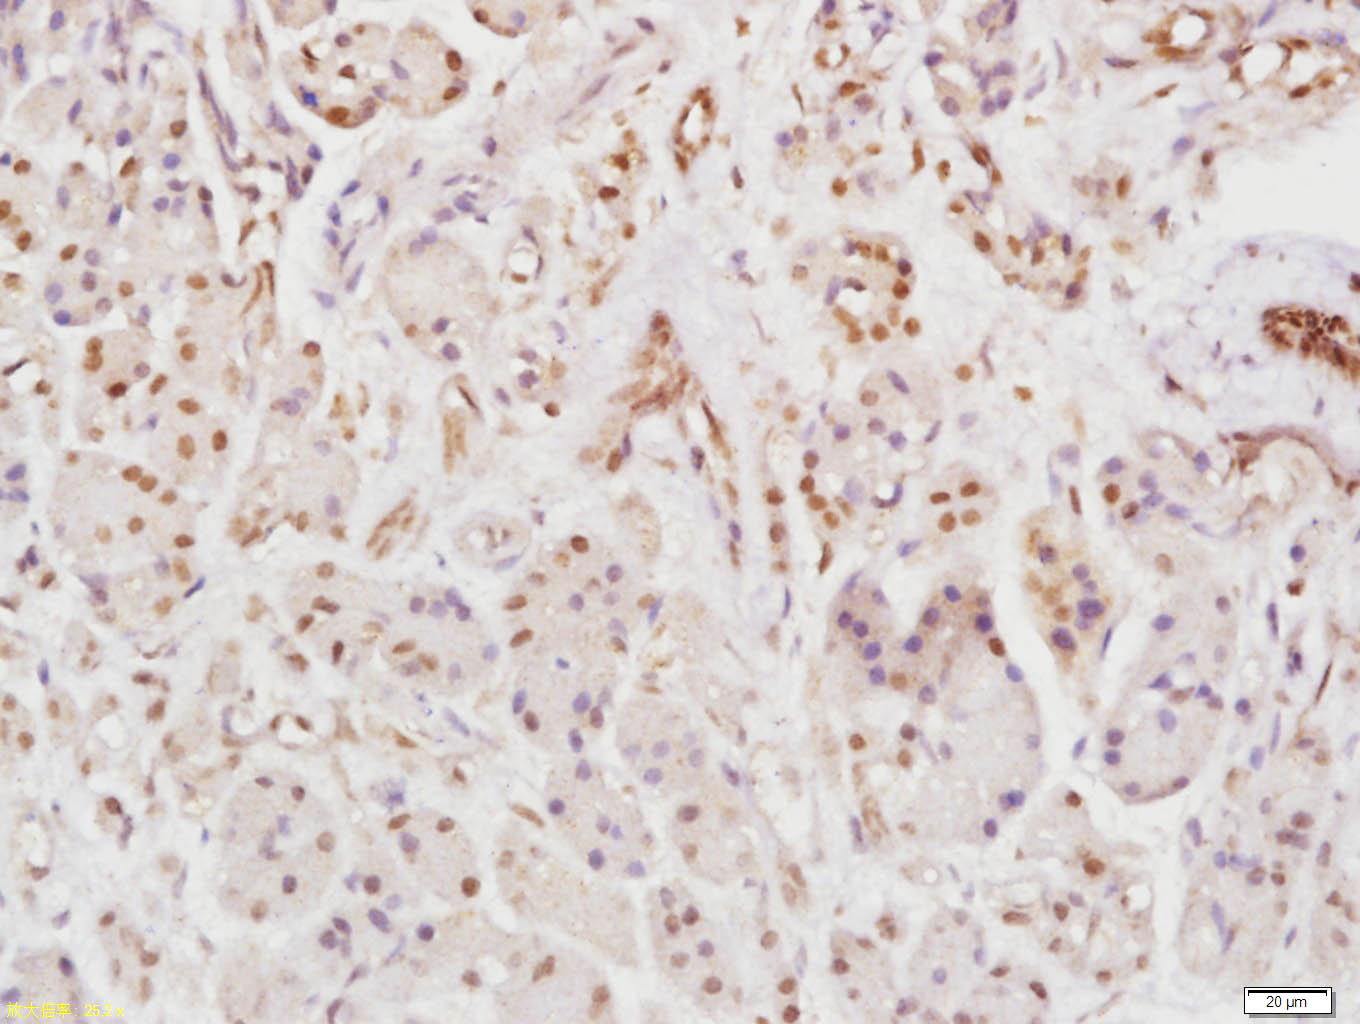

Paraformaldehyde-fixed, paraffin embedded (Human pancreatic cancer); Antigen retrieval by boiling in sodium citrate buffer (pH6.0) for 15min; Block endogenous peroxidase by 3% hydrogen peroxide for 20 minutes; Blocking buffer (normal goat serum) at 37°C for 30min; Antibody incubation with (Rho B) Polyclonal Antibody, Unconjugated (bs-11142R) at 1:400 overnight at 4°C, followed by operating according to SP Kit(Rabbit) (sp-0023) instructions and DAB staining.